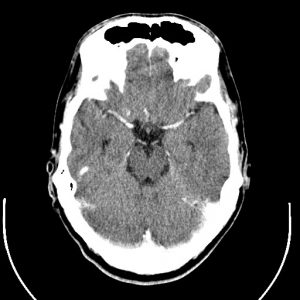

Para cada técnica de imágenes médicas, hay algoritmos especializados, ya que las características de las imágenes son diferentes, y su interpretación también. Por ejemplo, las imágenes de tomografía axial computarizada (TAC) pueden parecerse a las imágenes de resonancia magnética, sin embargo, la información que contienen es muy diferente, como se muestra a continuación.

Imágenes de TAC: se generan empleando rayos x y las formas e intensidades que se observan están relacionadas con la morfología y propiedades físicas de las estructuras anatómicas.

Imágenes de Resonancia: se crean a partir de campos magnéticos y contienen información relacionada con la actividad metabólica y el funcionamiento de los órganos y tejidos.

examen resonancia magnetica tac de cerebro examen resonancia magnetica tac de cerebro 2

Izquierda: imagen de resonancia magnética del cerebro. Derecha, TAC del cerebro